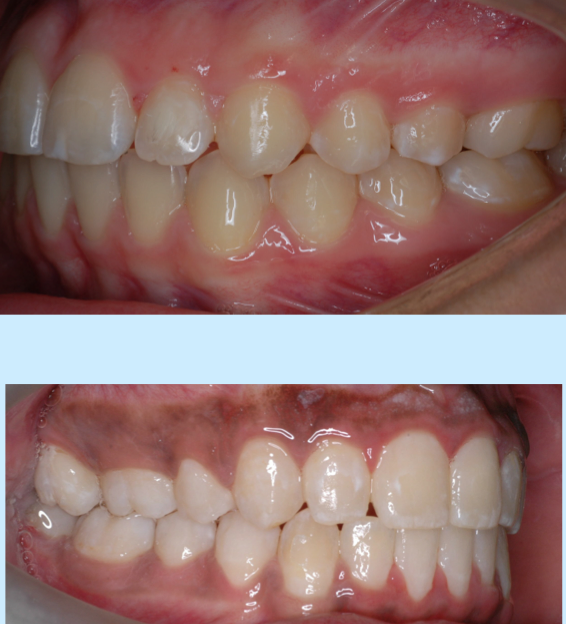

class 1

class 2

class 1 malocclusion

class 2 malocclusion

full step class 2

end-on class 2

class 2 subdivision right